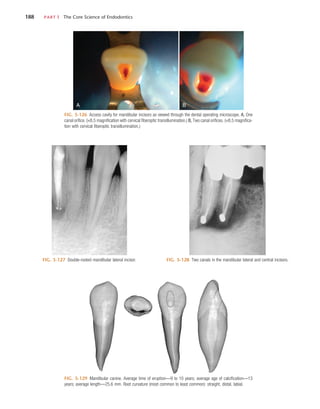

odontic explorer can be used to probe the depth of the access,

using magnification or the DOM. Often a small opening into

the chamber is present, or the dentin is very thin and the

explorer penetrates into the chamber. The depth and angle of